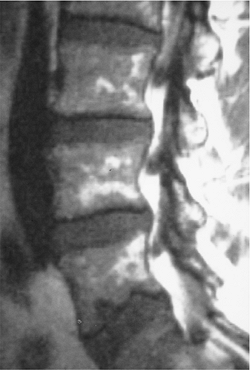

FIGURE 10-40 Sagittal T1-weighted image of the lumbar spine showing diffuse marrow infiltration caused by multiple myeloma.